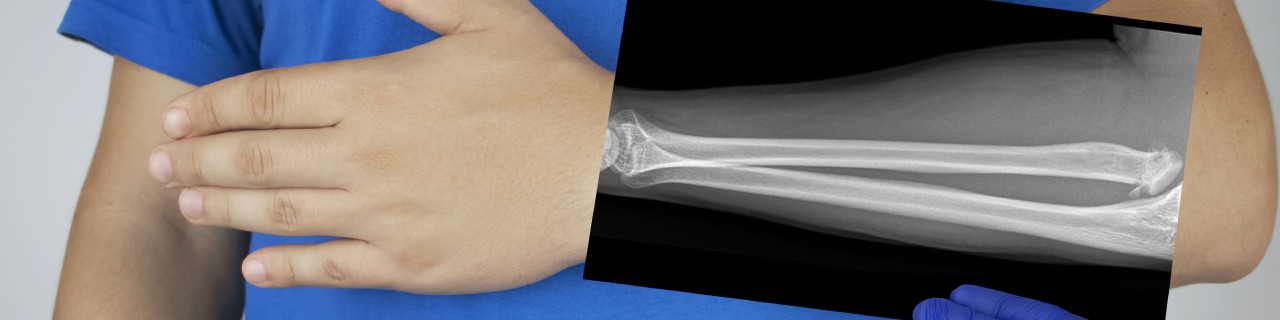

The most common symptoms of minor fractures can include severe pain, swelling and difficulty moving the injured area. Your doctor may need to perform an x-ray to determine the severity of the break in order to recommend the appropriate treatment. It can take up to eight weeks for minor fractures to heal. While you are healing, you may be asked to refrain from activities that could cause further strain. In some cases, you may need surgery, depending on where the fracture has occurred.